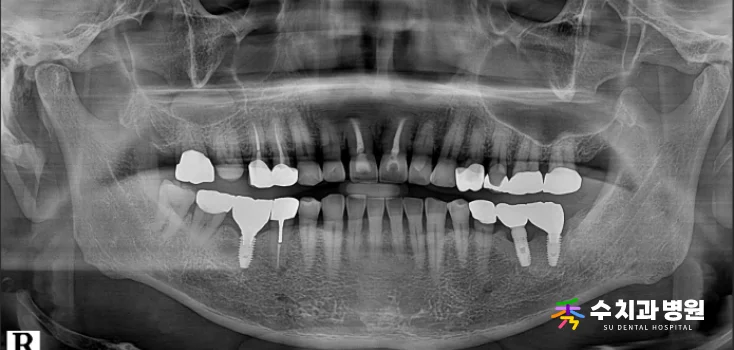

[치료 전 엑스레이 사진] (촬영일: 2024년 09월)

정밀 검사 결과, 오른쪽 대문니(앞니)는

과거에 신경치료를 받았던 이력이 있었습니다.

뿌리 쪽 잇몸뼈 흡수가 심하게 진행되어

치아가 제 위치를 잡지 못하고 있었습니다.

치아가 심하게 흔들리는 상태였기 때문에

안타깝게도 발치가 불가피했습니다.